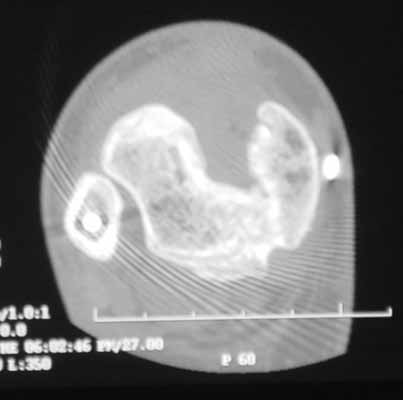

From what I can see on the flms you sent, that is a large void in the anterior aspect of the tibial metaphysis. I realize that she is assymptomatic now. I would be very worried about a stress fracture occuring in the remaining posterior cortex or worse through the unsupported anterior tibial plafond. I would bone graft her now and allow her to weight bear as tolerated to fill in the defect and protect the reconstructed joint.

It looks like there is a wedge shaped (1 cm by 2cm) bone defect of the anterior tibia about 3 cm proximal to the joint with sclerotic margins and the osteocet turned to fibrous tissue rather than bone. I've seen that kind of defect when I've used an osteotome to lever down an impacted anterior articular surface. If the soft tissue allows, that defect should respond well to autologous cancellous grafting with perhaps drilling through the sealing callus.